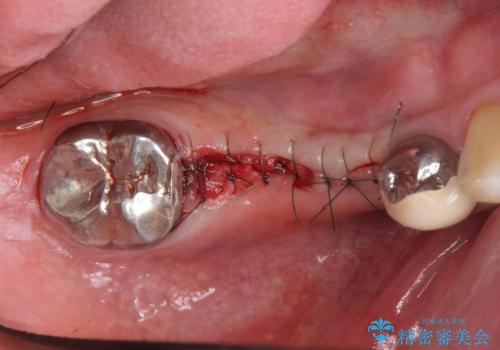

長いブリッジをインプラント補綴への変更

- 右下に入れた長いブリッジが噛むといたみ、改善を希望され来院されました。

長いブリッジは支台となる歯の過大な負担となることが多く、歯の破折や揺れ・痛みの原因となり得ます。

支台を増やし、残った歯の負担を減らし守るために欠損部位にインプラントを埋入し咬合力の負担に対応できる環境を整えます。